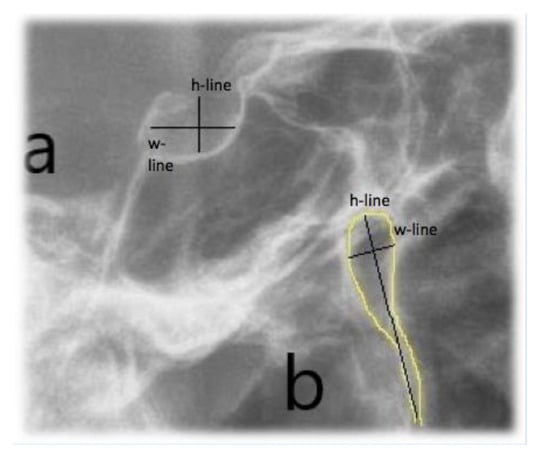

Lateral cephalometric radiographs were used to measure skeletal relationship angle (ANB) and evaluate PP (Figure 1), sella bridging (Figure 2) and atlas posterior arch deficiency (Figure 3).

The extent of PP osseous anomaly of the atlas vertebra was estimated following the classifications of Cederberg and Stubbs [14,15]: Grade 1—the absence of calcification, Grade 2—the presence of calcifications which extend for less than half the distance between the posterior segment of the upper articular process and the lateral and posterior segment of the superior portion of the posterior atlas arch, Grade 3—calcifications which extend for more than half the distance between the posterior portion of the superior articular process and the posterolateral portion of the upper margin of the posterior arch of the atlas but which do not form a complete ring, Grade 4—calcifications forming a complete bone ring.

Figure 1. Ponticulus posticus (PP) full ring.